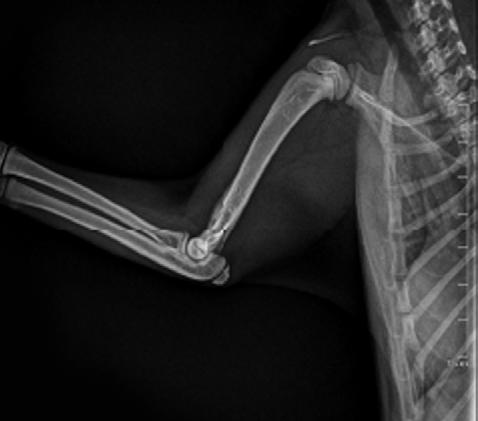

Four weeks later, Hotch was presented with marked lameness and a firm marked swelling of his left antebrachium. There were no obvious wounds or scabs, although he was hyperthermic. He was admitted for radiographs (see images) under sedation (dexmedetomidine 5µg/kg, methadone 0.3 mg/kg).

1

Radiographs showed signs of acute suppurative osteomyelitis, likely bacterial. This has a characteristic appearance in kittens, as the periosteum is not so strongly attached to the bone cortex, and the neutrophilic exudate lifts the periosteum, which then makes a florid new bone response ( blue arrow). Usually, these infections arise after a bite wound. The periosteal new bone formation is florid. Patchy portions of cortical bone lysis (yellow arrow) are also evident towards the centre of the lesion. At this stage we contacted Dr Richard Malik at the CVE as I had never seen anything like this before. Richard was also concerned about mild nutritional secondary hyperparathyroidism (NSH) due to the bone cortices appearing pale (osteopaenic), with an area of increased relative radiodensity immediately next to the growth plates (orange arrow). In NSH, the only normal bone is that laid down by endochondral ossification at the growth plates (and in this case—where new bone is laid down to wall off the infected bone), the rest of the skeleton is being broken down by osteoclasts under the direction of PTH.

Figure 1. Radiographs of the affected limb at presentation